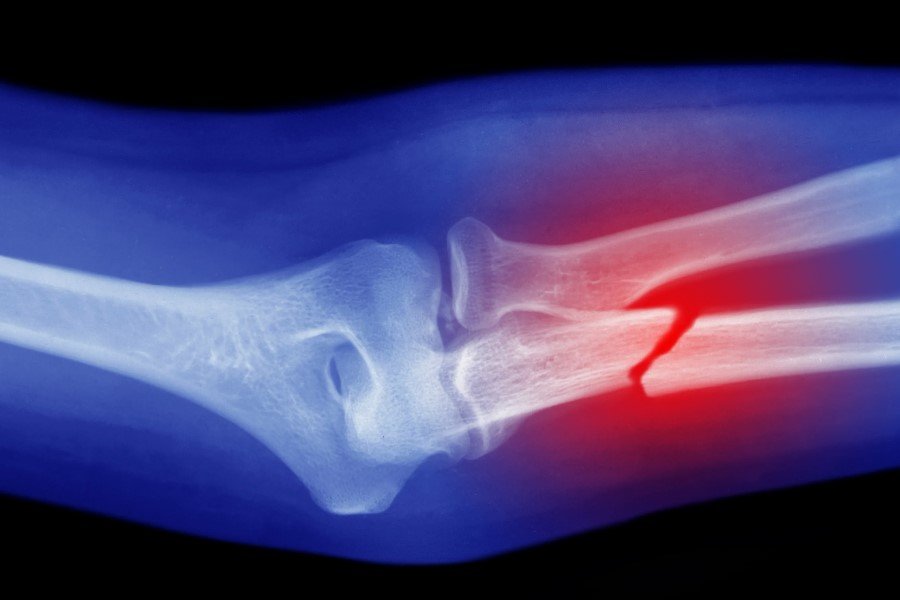

Як лікарі визначають перелом

Зараз медицина може все. Рентген — класика, але якщо складно — КТ, МРТ поруч. Лікар оглядає, оцінює рухи, реакцію на біль, форму кінцівки. Важливо: не лише виявити перелом, а зрозуміти його природу. Це не просто №1, це важливо для лікування. Операція чи гіпс? Все залежить. Але головне — повернути кістці її силу і форму. Без цього — ніяк.